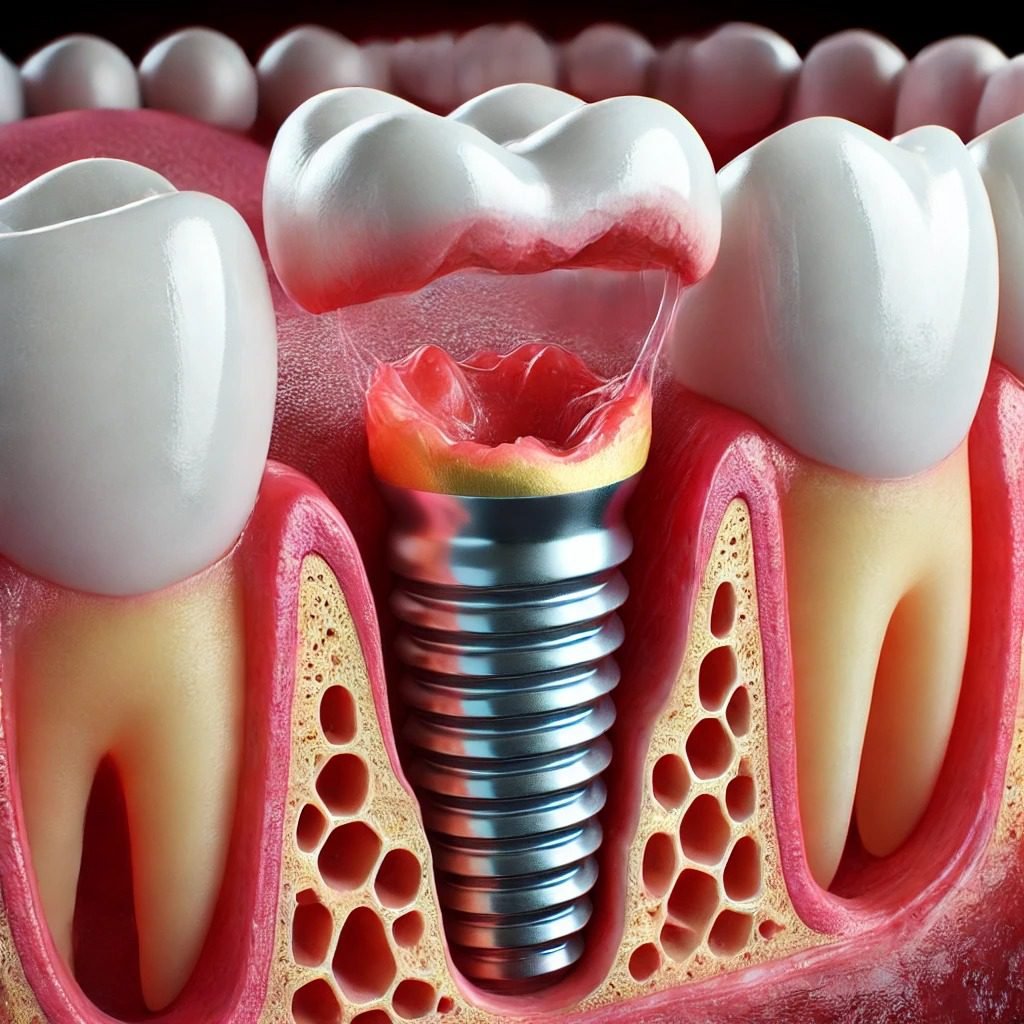

Zahnimplantate

Zahnimplantate

Zahnimplantate bieten eine moderne und effektive Lösung für den Ersatz fehlender Zähne. Hier ein Überblick über die wichtigsten Aspekte: